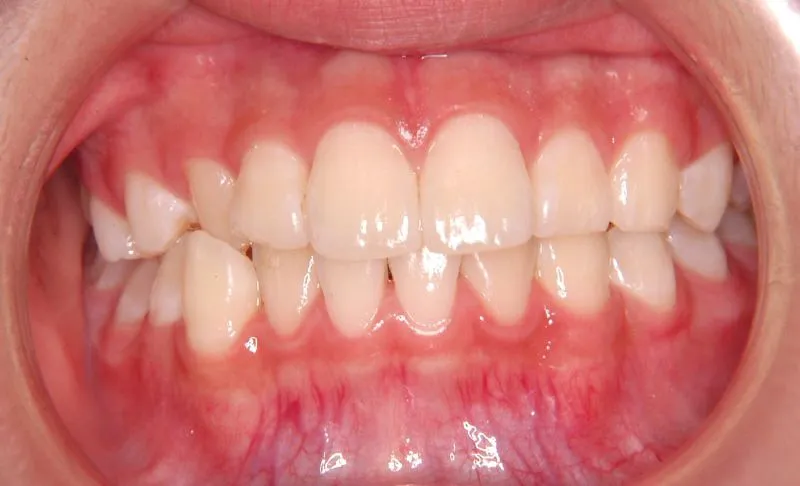

初診時

初診時年齢 小学校6年生 (女性) 主訴 犬歯がずれている・噛み合わない

診断名 叢生・交叉咬合 装置名

右下の犬歯がずれて生え噛み合わせの邪魔をしています。

歯は抜かず、上下マルチブラケット装置を使用し治療いたしました。

治療回数54回、9年3ヶ月の治療期間で矯正治療を終了しました。

噛み合わせのずれは、ぱっと見綺麗に見えますが、放っておくとのちのち噛みにくくなり、顎関節にまで影響を及ぼしかねません。